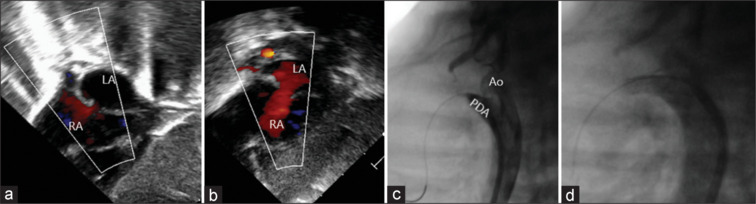

大多数产前发现d型大动脉转位并室间隔完整(TGA-IVS)的新生儿术前病程相对标准,但一些卵圆孔(FO)或动脉导管受限的患者出生后容易出现严重的低氧血症,在出生后数小时内死亡风险显著。含氧血和缺氧血混合不良会导致严重的紫绀和死亡。我们报告了两名产前诊断为TGA-IVS的新生儿,他们表现出明显的去饱和,需要紧急气囊房间隔造口术(BAS)。在这两个病人中,混合的结果是不充分的;导管支架植入必须恢复氧合。这些病例强调了产前识别TGA-IVS胎儿的高危特征的重要性,如限制性FO或导管收缩。尽管在解剖学上有足够的BAS,但这些婴儿中有一小部分混合不充分,可以在手术前通过导管支架植入进一步稳定。

Most neonates with prenatally detected d-transposition of great arteries with intact ventricular septum (TGA-IVS) have a relatively standard preoperative course, but some patients with restrictive foramen ovale (FO) or ductus arteriosus tend to have severe hypoxemia after birth, posing a significant risk of mortality in the first few hours after birth. Poor mixing of oxygenated and deoxygenated blood leads to severe cyanosis and death. We present two prenatally diagnosed neonates with TGA-IVS who presented with significant desaturation, necessitating emergency balloon atrial septostomy (BAS). In both patients, the resultant mixing was inadequate; ductal stenting had to be resorted to restore oxygenation. These cases highlight the importance of prenatal identification of high-risk features, such as restrictive FO or ductal constriction, in fetuses with TGA-IVS. A small proportion of these babies who have inadequate mixing despite an anatomically adequate BAS can be further stabilized before surgery by means of ductal stenting.